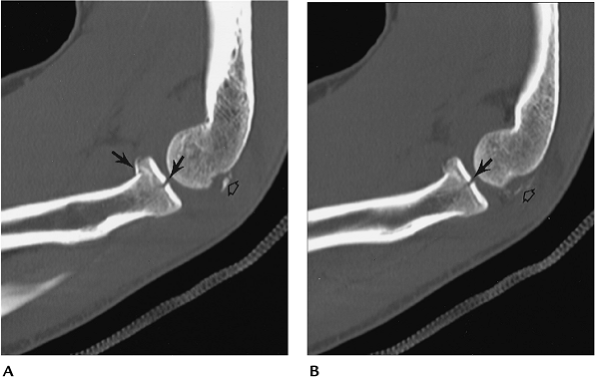

![]() |

FIGURE 8-10 CT images in the sagittal plane (A,B) demonstrate a minimally displaced comminuted radial head fracture (arrows) with associated capitellar fragments (open arrow).